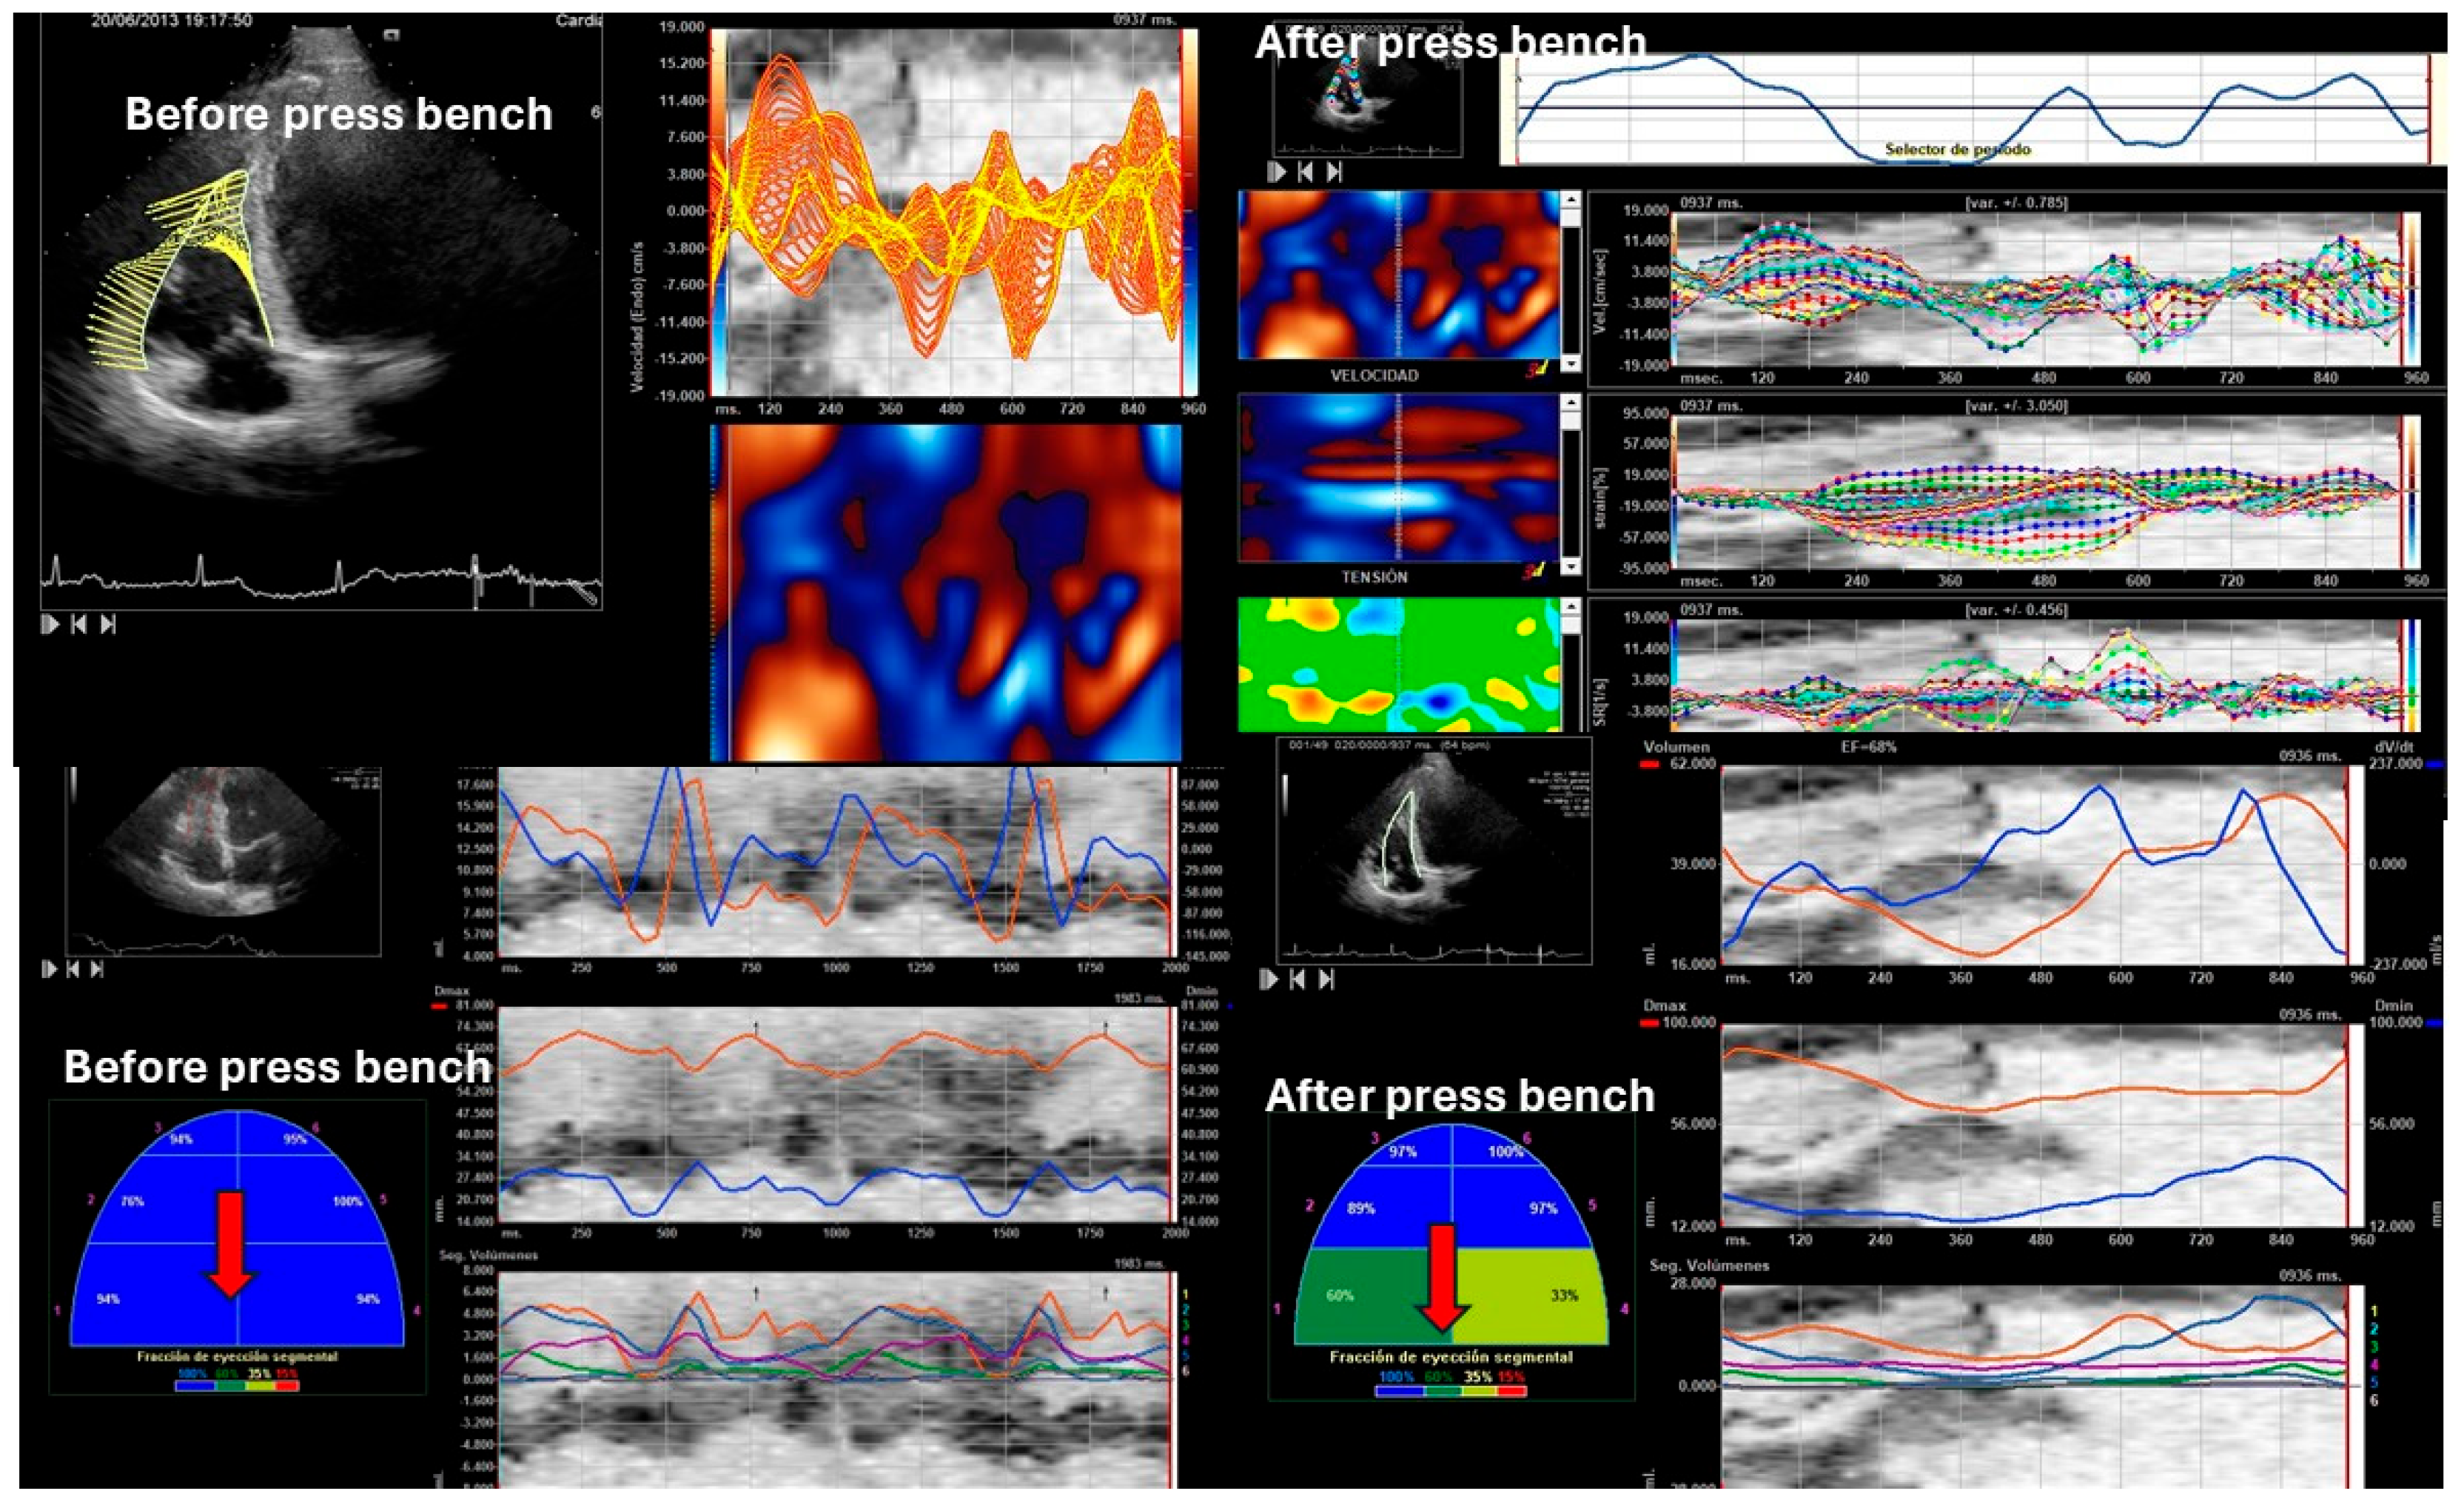

3.4. Right Ventricular Systolic Function

| 3D RVEF (%) | 0.67 ± 0.06 | 0.55 ± 0.22 | 0.78 ± 0.12 | 0.001 |

| IVA (m/s2) | 2.38 ± 0.22 | 3.52 ± 0.15 | 6.66 ± 0.88 | 0.001 |

| S’ wave (cm/s) | 12.27 ± 1.13 | 14.52 ± 0.09 | 18.38 ± 1.21 | 0.001 |

| TAPSE (mm) | 24.33 ± 3.12 | 19.08 ± 5.14 | 27.45 ± 3.21 | 0.001 |

| Global RVEF 2D | 0.62 ± 0.15 | 0.49 ± 0.06 | 0.74 ± 3.21 | 0.001 |

| Laterobasal RVEF | 0.65 ± 0.25 | 0.42 ± 0.02 | 0.94 ± 0.17 | 0.001 |

| Lateromedial RVEF | 0.62 ± 0.12 | 0.55 ± 0.18 | 0.74 ± 0.22 | 0.001 |

| Lateroapical RVEF | 0.62 ± 0.09 | 0.49 ± 0.17 | 0.95 ± 0.19 | 0.001 |

| Septoapical RVEF | 0.63 ± 0.15 | 0.47 ± 0.18 | 0.95 ± 0.21 | 0.001 |

| Septomedial RVEF | 0.65 ± 0.21 | 0.46± 0.22 | 0.98 ± 0.17 | 0.001 |

| Septobasal RVEF | 0.58 ± 0.22 | 0.43 ± 0.02 | 0.94 ± 0.19 | 0.001 |

| Peak systolic longitudinal velocity (cm/s) | 4.98 ± 0.12 | 4.01 ± 10.21 | 9.48 ± 3.25 | 0.001 |

| peak E longitudinal velocity (cm/s) | −5.6 ± 1.35 | −4.2 ± 0.87 | −7.38 ± 3.15 | 0.0001 |

| peak A longitudinal velocity (cm/s) | −4.01 ± 0.74 | −3.75 ± 0.98 | −5.14 ± 1.48 | 0.0001 |

| Peak systolic radial velocities (cm/s) | 4.76 ± 0.48 | 1.76 ± 0.48 | 6.17 ± 1.35 | 0.0001 |

| E peak radial velocity (cm/s) | −1.75 ± 0.16 | −1.45 ± 0.54 | −2.21 ± 0.191 | 0.0001 |

| A peak radial velocity (cm/s) | −0.11 ± 0.12 | −0.09 ± 1.35 | −0.6 ± 0.22 | 0.0001 |

| Right ventricular longitudinal global strain (%) | −27.31 ± 1.47 | −23.55 ± 2.37 | −30.98 ± 2.12 | 0.0001 |

| Right ventricular Longitudinal Strain delay (ms) | 144.88 ± 22.52 | 168.92± 29.35 | 98.27 ± 12.11 | 0.0001 |

| Right ventricular longitudinal global right Strain rate (1/s) | −1.79 ± 0.078 | −1.48 ± 0.33 | −2.88 ± 0.25 | 0.0001 |

| Right ventricular Longitudinal systolic displacement (mm) | 6.12 ± 1.18 | 5.09 ± 3.22 | 10.88 ± 1.25 | 0.0001 |

| Right ventricular Radial systolic displacement (mm) | 1.88 ± 1.78 | 1.33 ± 1.14 | 4.57 ± 0.96 | 0.0001 |

| Right ventricular Radial displacement delay (ms) | 182.14 ± 17.12 | 212.36 ± 18.96 | 124.32 ± 15.25 | 0.0001 |